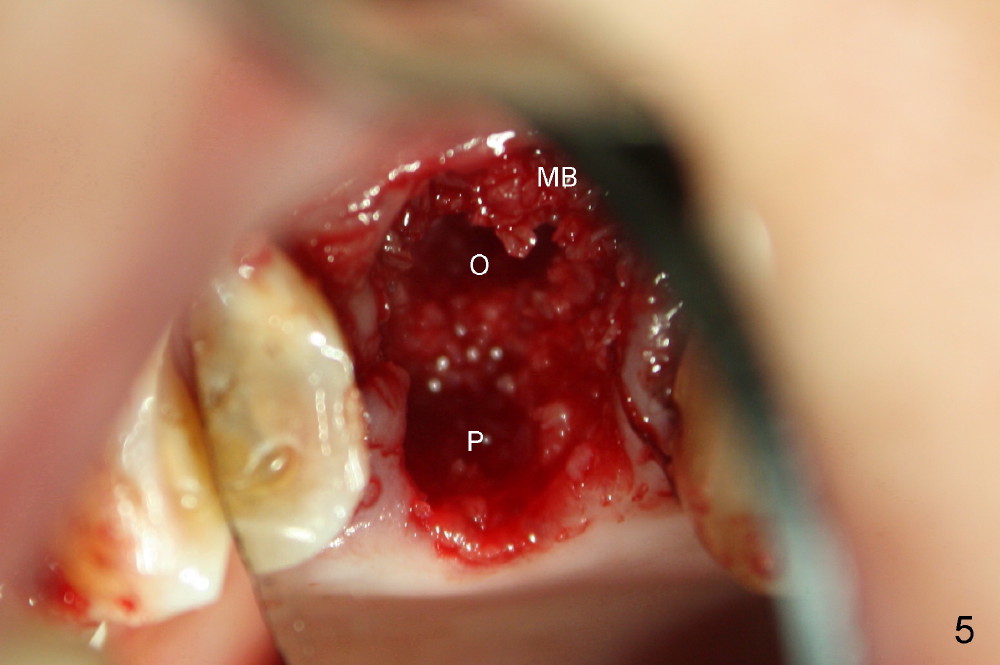

A 66-year-old lady requests restoring a broken tooth (Fig.1). Osteotomy is initiated in a thin septum (Fig.2 (occlusal mirror view) S) by sectioning, drilling and tapping (Fig.3 T). When 7x17 mm tap is removed, the osteotomy is found to form basically in the middle of socket (Fig.4 O). The apical portion of three sockets (Fig.5: MB, P and DB (not labeled) is packed with mixture of autogenous bone and allograft. When a 7x14 mm implant is placed, there are buccal and lingual gaps (Fig.6 *). The latter are bone grafted again (Fig.8 *) and require a coverage. After placement of a 4x3 mm abutment (Fig.7,8 A), an immediate provisional is fabricated (Fig.9 tissue surface view) to cover the remaining sockets (Fig.10 (occlusal mirror view), 11 (buccal view)). The provisional is infra-occlusal, i.e., load-free (Fig.11). The buccal and lingual aspects of the socket are covered by fresh epithelium 8 days postop (Fig.12 <). The implant appears to have osteointegrated 4 months postop (Fig.13). The tooth #16 appears to have shifted mesially. It is difficult to prepare for #15 crown. Luckily the patient agrees to have it extracted because of persistent sensitivity after MO composite. The definitive crown at the site of #15 is cemented 6 months postop (Fig.14).